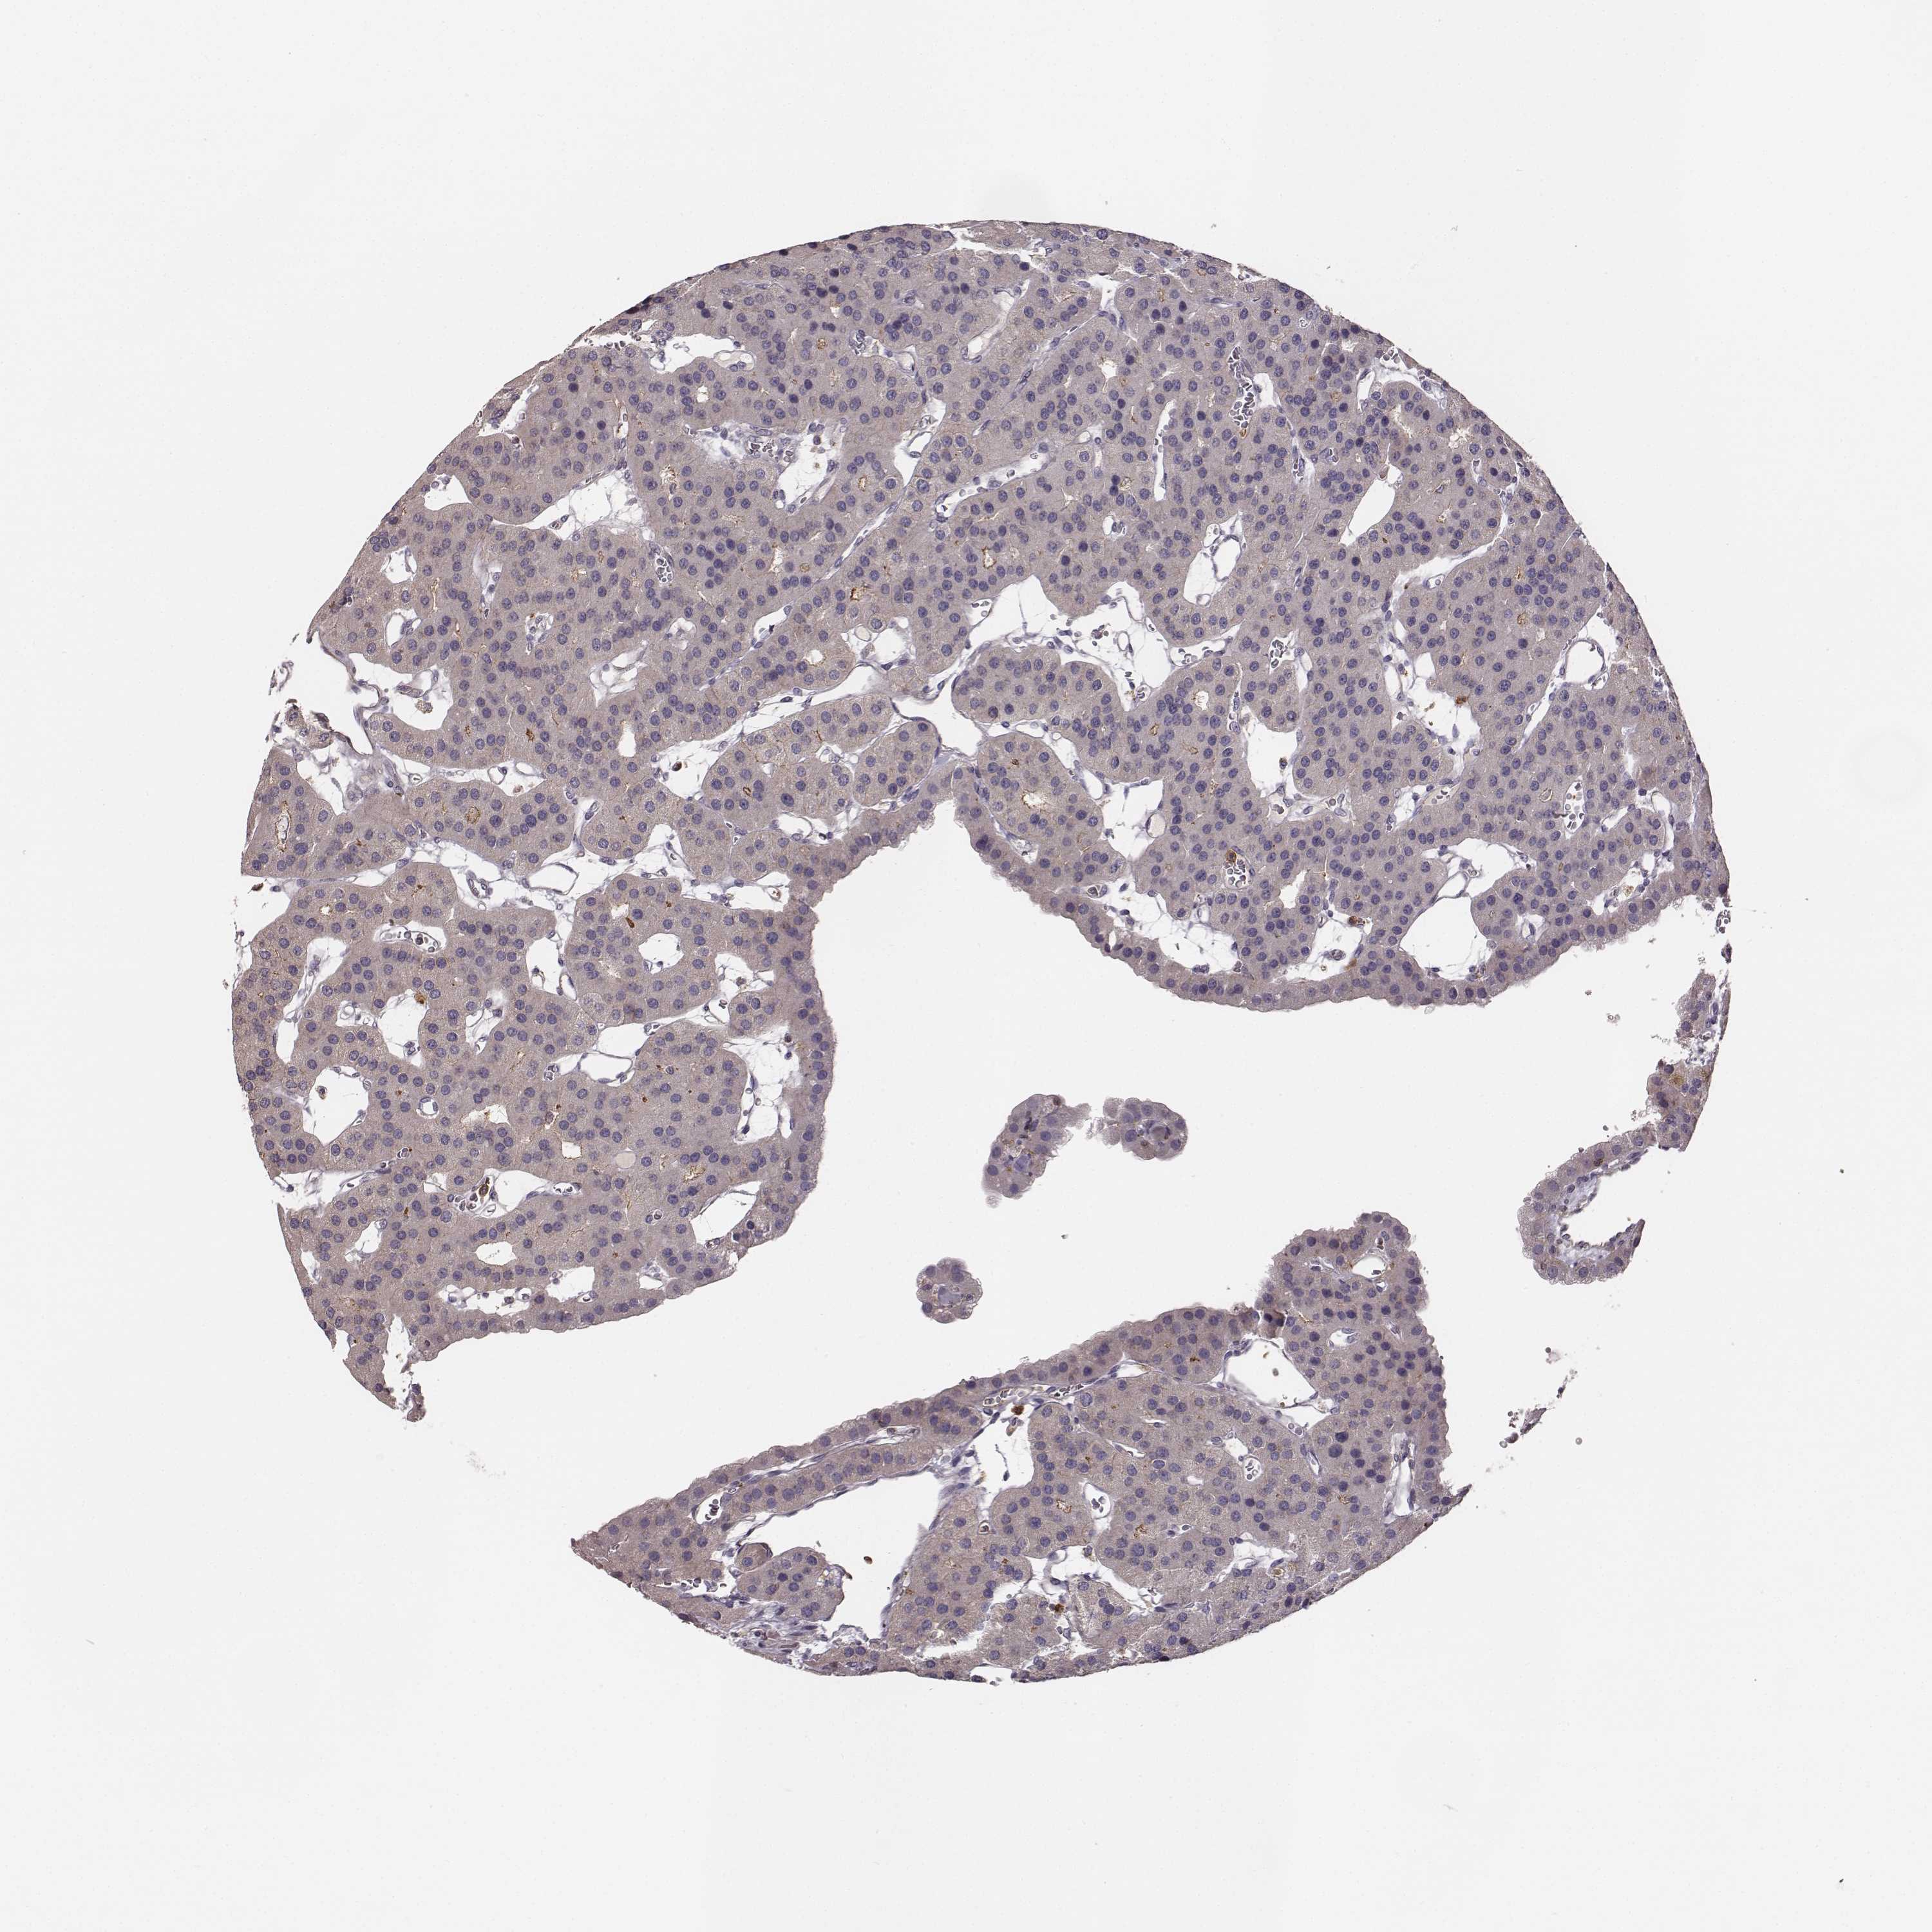

TISSUE PRIMARY DATA PARATHYROID GLAND Show tissue menu

Parathyroid gland

PARATHYROID GLAND - Expression summary

PARATHYROID GLAND - Antibody stainingi

Antibody staining in the annotated cell types in the current human tissue is reported as not detected, low, medium, or high, based on conventional immunohistochemistry profiling in selected tissues. This score is based on the combination of the staining intensity and fraction of stained cells.

Each image is clickable and will lead to virtual microscopy that enables deeper exploration of all samples and also displays staining intensity scores, fraction scores and subcellular localization as well as patient and tissue information for each sample.

Antibody HPA004835Antibody HPA073497Antibody CAB009321Antibody CAB075747

Glandular cells Not detectedNot detectedLowNot detected